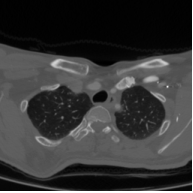

These typical loss functions define the loss of each pixel only on its true and predicted values, but not considering those of other pixels, and aggregate them by weighted averaging or summing without considering the spatial relations between the predictions. Since this type of definition is of local nature, these loss functions may not sufficiently impose a network to learn the shape of an object or the geometry between multiple objects, especially when the amount of training data is small. On the other hand, the ability of the network to learn the shape may be important for better segmenting the objects in medical images since these objects typically have an expected shape or a geometry due to their intrinsic characteristics. One example is the formation of the aortic arch and great vessels in a human body. The aorta and the large arteries and veins (also known as great vessels) are not randomly distributed over the human body. Instead, they are found in a particular geometry due to the human anatomy (Figure 1). Besides, they mostly seem as round objects on a 2D axial image since blood vessels are tubular in 3D. This anatomic information is indeed utilized by human annotators to locate these vessels and delineate their boundaries.

The proposed topology-aware loss function was tested on a dataset that contains CT scans of 24 subjects with prediagnosis of pulmonary embolism. The CT scans were acquired using a 128 slice Philips Ingenuity CT scanner with 1.5 mm slice thickness. A 60 ml of non-ionic contrast material (iohexol; generic name Opaxol) was introduced with a 100 ml saline chaser at 5 ml/s. The data collection was conducted in accordance with the tenets of the Declaration of Helsinki and was approved by Koc University Institutional Review Board (Protocol number: 2022.161.IRB1.064). We randomly split the 24 subjects into the training and test sets. The training set contains 2896 images of 16 subjects; 2234 images of 12 subjects were used to learn the network weights by backpropagation and 662 images of 4 subjects were used as validation images for early stopping. The test set comprises 1431 images of 8 subjects; note that the images of none of these subjects were used neither in the training nor for early stopping.